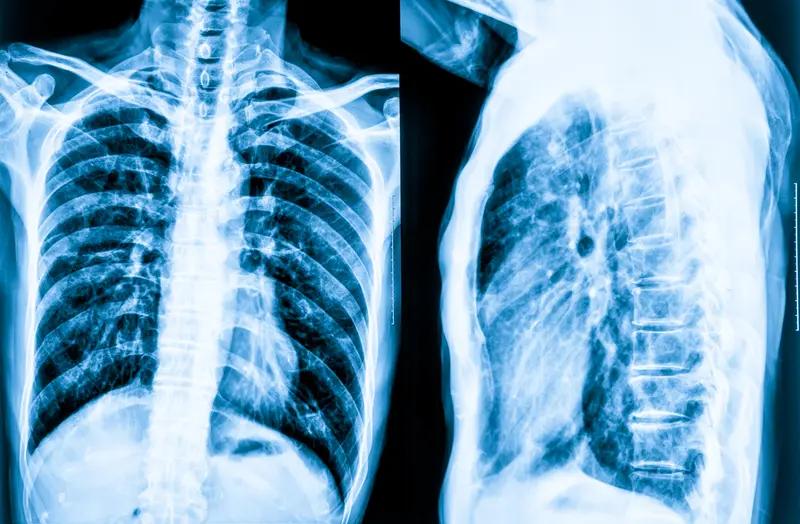

中老年体检,选对项目很重要,它们就是健康“守门人”。 胸部CT平扫(薄层扫描)得安排上,中老年是肺癌高发群体,早期肺癌没明显症状,普通胸片易漏小病变,薄层CT能精准识别几毫米的结节,早发现早干预。 13碳呼气试验也不能少,肠胃功能弱的中老年人适合做,吹口气就能检测幽门螺杆菌,这菌和胃炎、胃癌等有关。 颈部动脉彩超(8根血管)能评估血管情况,及时发现斑块和狭窄,预防脑梗中老年体检